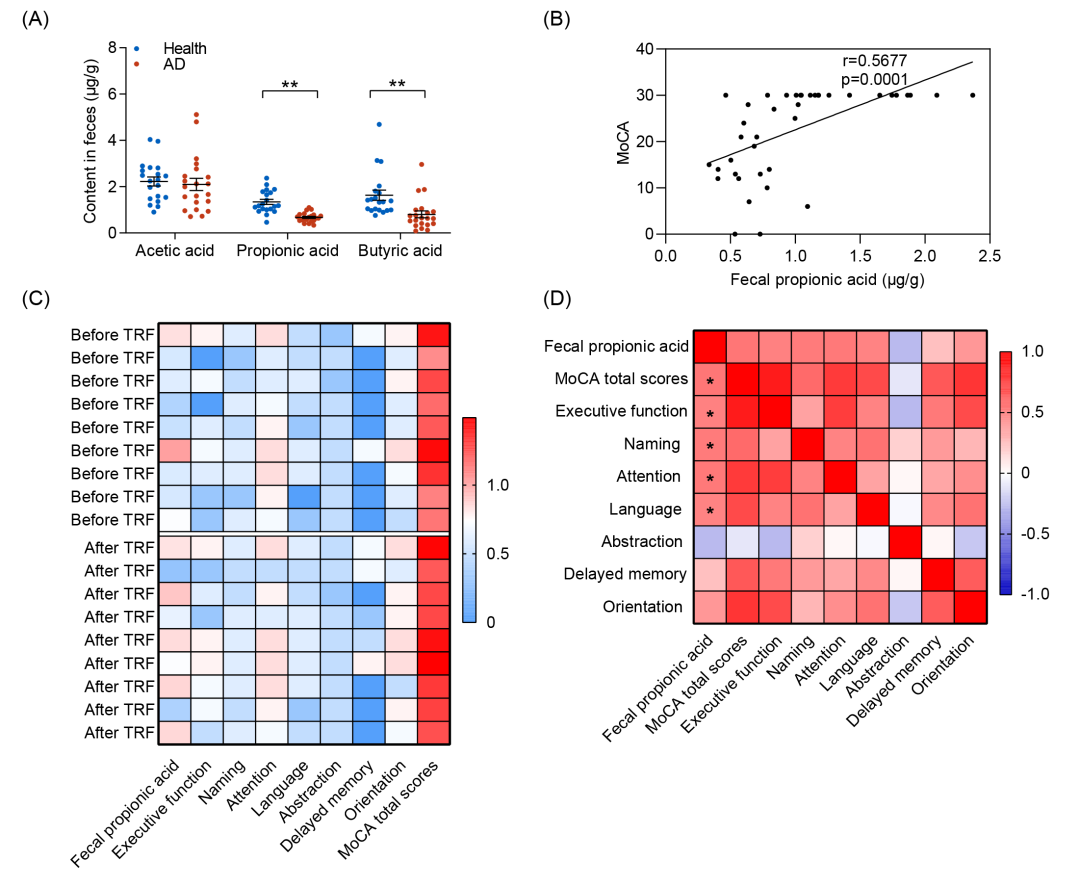

为了研究SCFAs是否可作为AD的潜在生物标志物,本研究开展了一项病例对照研究,分析了AD患者(n = 21)和健康受试者(n = 20)粪便中PA和丁酸的浓度(表 S4)。认知功能评估结果表明,与健康个体相比,AD患者的认知能力显著下降,其蒙特利尔认知评估量表(MoCA)及简易精神状态检查(MMSE)评分均明显降低(表S4)。结果显示AD患者粪便中PA水平显著低于健康受试者(图7A)。相关性分析进一步揭示,粪便PA浓度与认知功能呈显著正相关(图7B 和图S9A、B)。此外,粪便丁酸水平同样与认知功能呈显著正相关,尽管其相关系数低于PA(图 S9C、D)。

为进一步明确TRF对PA水平的影响以及其在缓解AD认知障碍中的作用,本研究检测图1中提到的4个月TRF临床干预前后的AD患者粪便PA水平(图S9E)。结果发现,粪便PA水平的提升与MoCA总分及多个特定认知领域(包括执行功能、命名、注意力和语言)呈显著正相关(图7C,D)。通过病例对照研究和小规模的TRF临床干预试验,本研究证实了粪便PA水平与认知状态呈显著正相关,提示PA可以作为AD的潜在生物标志物。

图7. PA作为AD患者的生物标志物在缓解认知障碍中发挥关键作用

(A)健康受试者与AD患者粪便中SCFAs水平的比较(n = 20-21);(B)散点图显示MoCA评分与粪便PA水平之间存在显著正相关(Pearson相关系数 r = 0.5677, p = 0.0001);(C)热图显示接受TRF治疗前后的AD患者粪便PA浓度和MoCA评分;(D)热图展示粪便PA水平变化与MoCA评分之间的Spearman秩相关分析结果。数据采用双尾Student’s t检验分析,*p < 0.05,**p < 0.01。